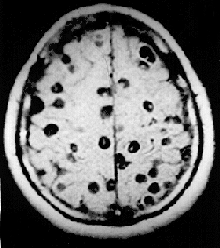

In 2000, an estimated 45 million people were infected with the beef tapeworm Taenia saginata and 3 million with the pork tapeworm Taenia solium.[45] Infection of the digestive system by adult tapeworms causes abdominal symptoms that, whilst unpleasant, are seldom disabling or life-threatening.[46][47] However, neurocysticercosis resulting from penetration of T. solium larvae into the central nervous system is the major cause of acquired epilepsy worldwide.[48] In 2000, about 39 million people were infected with trematodes (flukes) that naturally parasitize fish and crustaceans, but can pass to humans who eat raw or lightly cooked seafood. Infection of humans by the broad fish tapeworm Diphyllobothrium latum occasionally causes vitamin B12 deficiency and, in severe cases, megaloblastic anemia.[45]